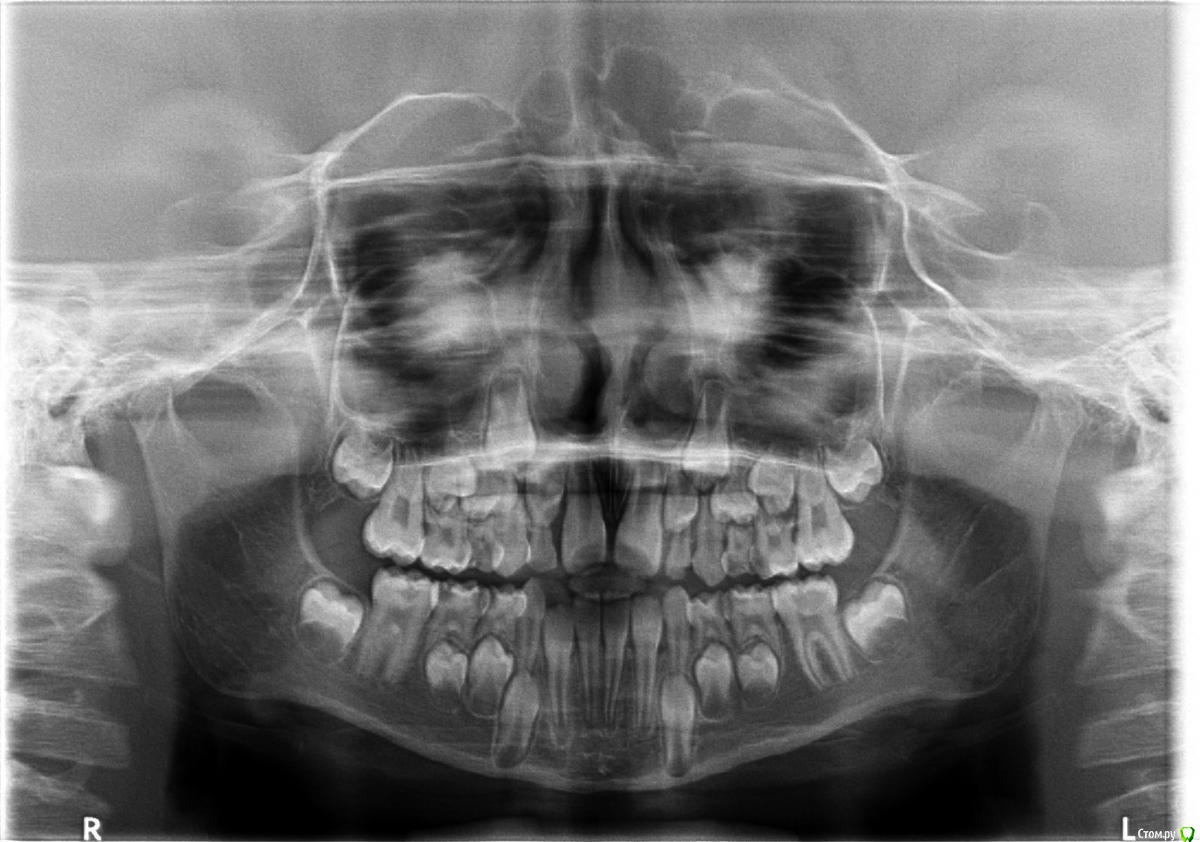

Лана30 Опубликовано 6 августа, 2015 Автор Поделиться Опубликовано 6 августа, 2015 Здравствуйте! Это панорамный снимок, который делали до лечения, после делали снимки, но я их не забрала. Посмотрите, пожалуйста, вылечили шестерку, пятерку и четверку которые на снимке справа снизу, а так слева. Если можно, Ваши дальнейшие рекомендации по лечению. Ссылка на комментарий

Yana guapa Опубликовано 10 августа, 2015 Поделиться Опубликовано 10 августа, 2015 (изменено) какая четверка? у вас их целых четыре- справа слева внизу и вверху. судя по снимку- скорей всего вверху?? как посоветовал Вам IvanK, нужен контрольный снимок после лечения - если все хорошо - то пусть постоит еще Ваша четверка. Им положено в 9-10 лет меняться. Если все таки заболит и надо будет удалять - то под контроль ортодонта (чтобы соседние зубы не сдвинулись и не заняли это место) Изменено 10 августа, 2015 пользователем Yana guapa 1 1 Ссылка на комментарий